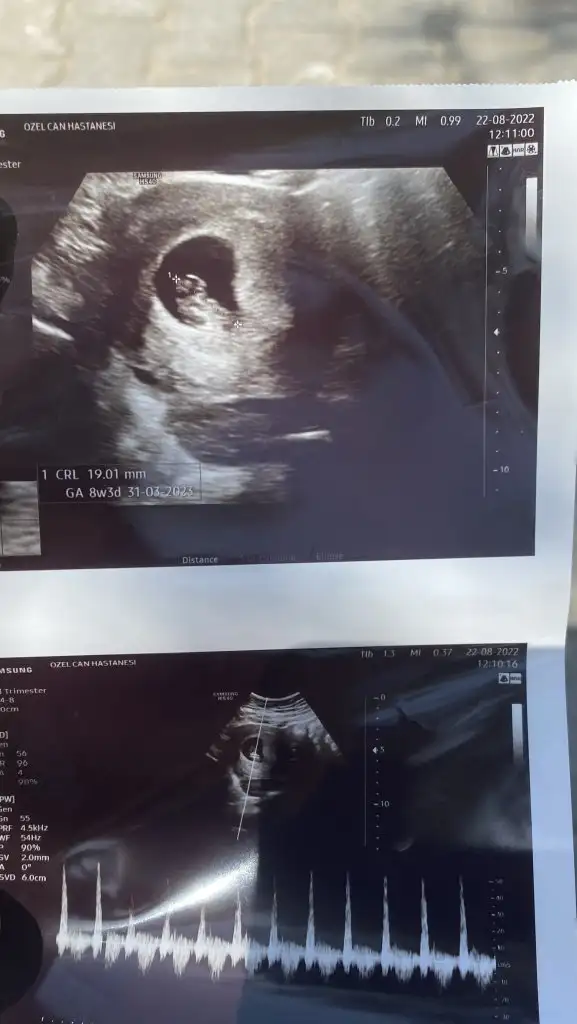

Ultrasonda bebeğin gözüktüğü resmî istiyorsanız yuvarlak değildi 7 haftalık ilken bu şekilde idi